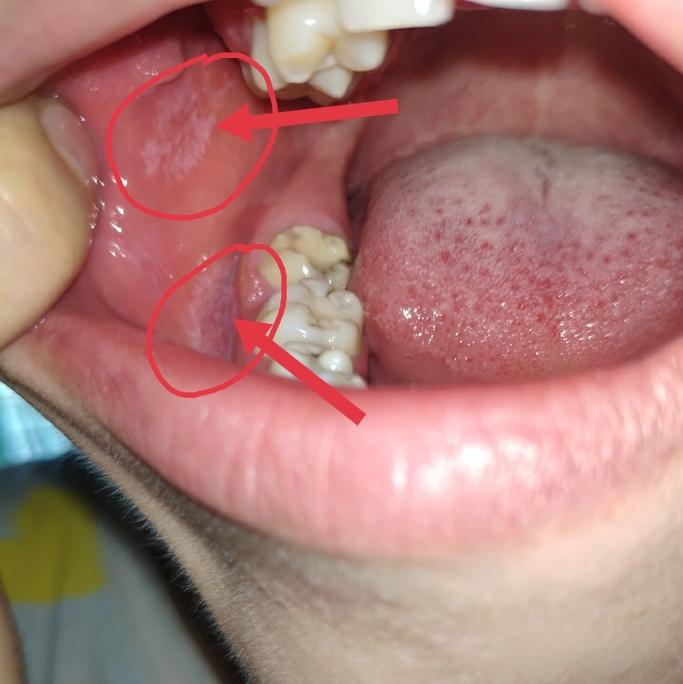

颊黏膜(最常见部位)

- 描述:通常在两侧脸颊内侧,对称出现,典型的表现为白色网纹,呈“树枝状”或“线状”,有时像“水波纹”,在白色条纹的末端,有时可见针头大小的白色或蓝色丘疹,称为“Wickham纹”,这是扁平苔藛的特征性表现。

- 图片关键特征:对称分布的白色网纹 + Wickham纹。